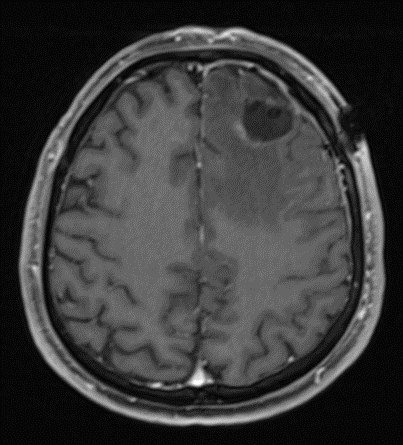

IRM préopératoire d’une lésion tumorale frontale gauche

IRM pré et post opératoire d’une lésion tumorale frontale gauche